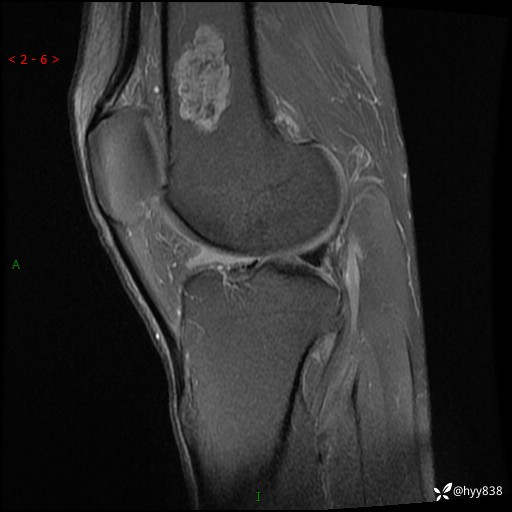

MRI

img

内生软骨瘤 (27)